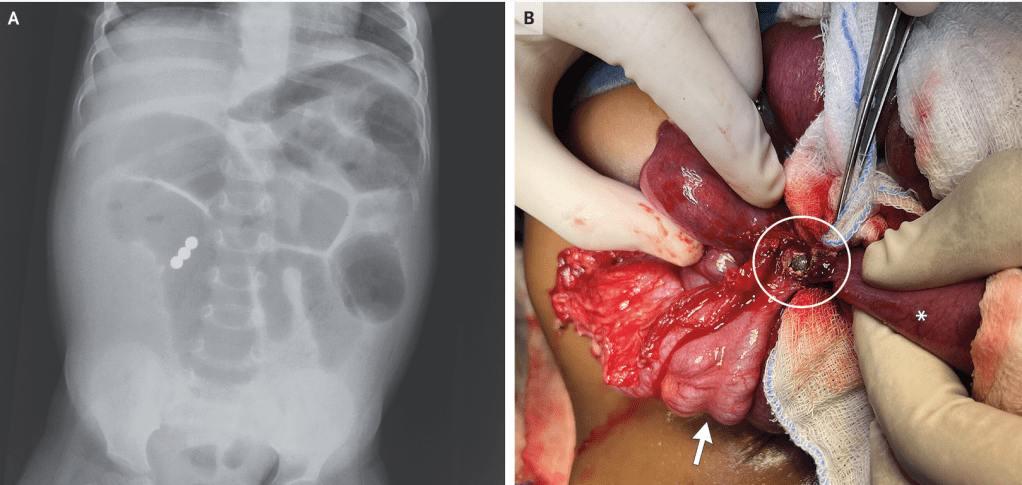

A previously healthy 18-month-old girl was brought to the emergency department with sudden-onset abdominal distention that had been preceded by 3 days of diarrhea and 1 day of vomiting…an emergency exploratory laparotomy was performed. An ileocecal fistula (Panel B, circle) created by the union of three magnetic beads was identified (arrow, cecum; asterisk, ileum), and dilated loops of bowel were noted. The bowel was repaired. The patient was discharged after five days.